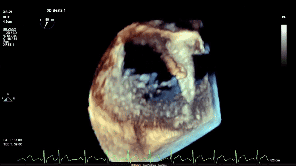

第一次夹合后3D

第一次夹合后3D彩

夹子释放后反流降至轻度

3D下组织桥稳定

3D下上彩